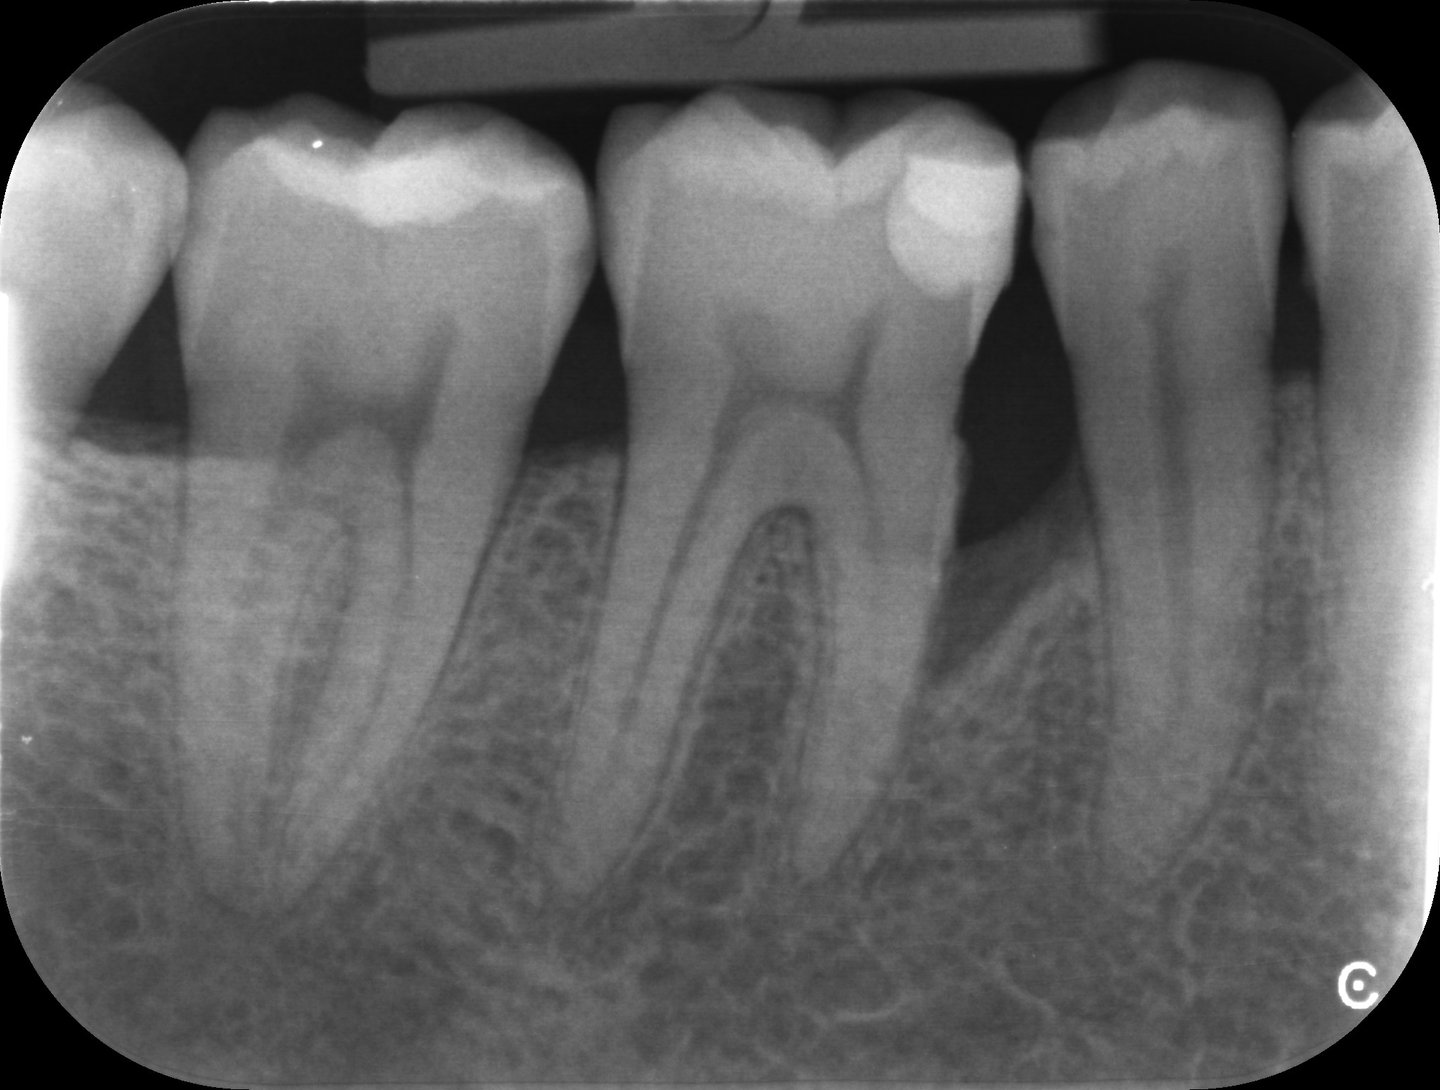

Parodontologie pour l'omnipraticien

Diagnostic et traitement